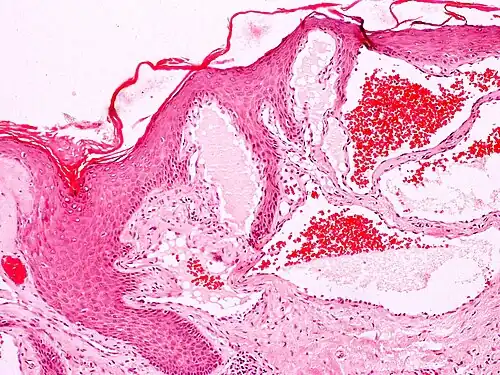

Histology

Angiokeratomas characteristically have large dilated blood vessels in the superficial dermis and hyperkeratosis (overlying the dilated vessels).